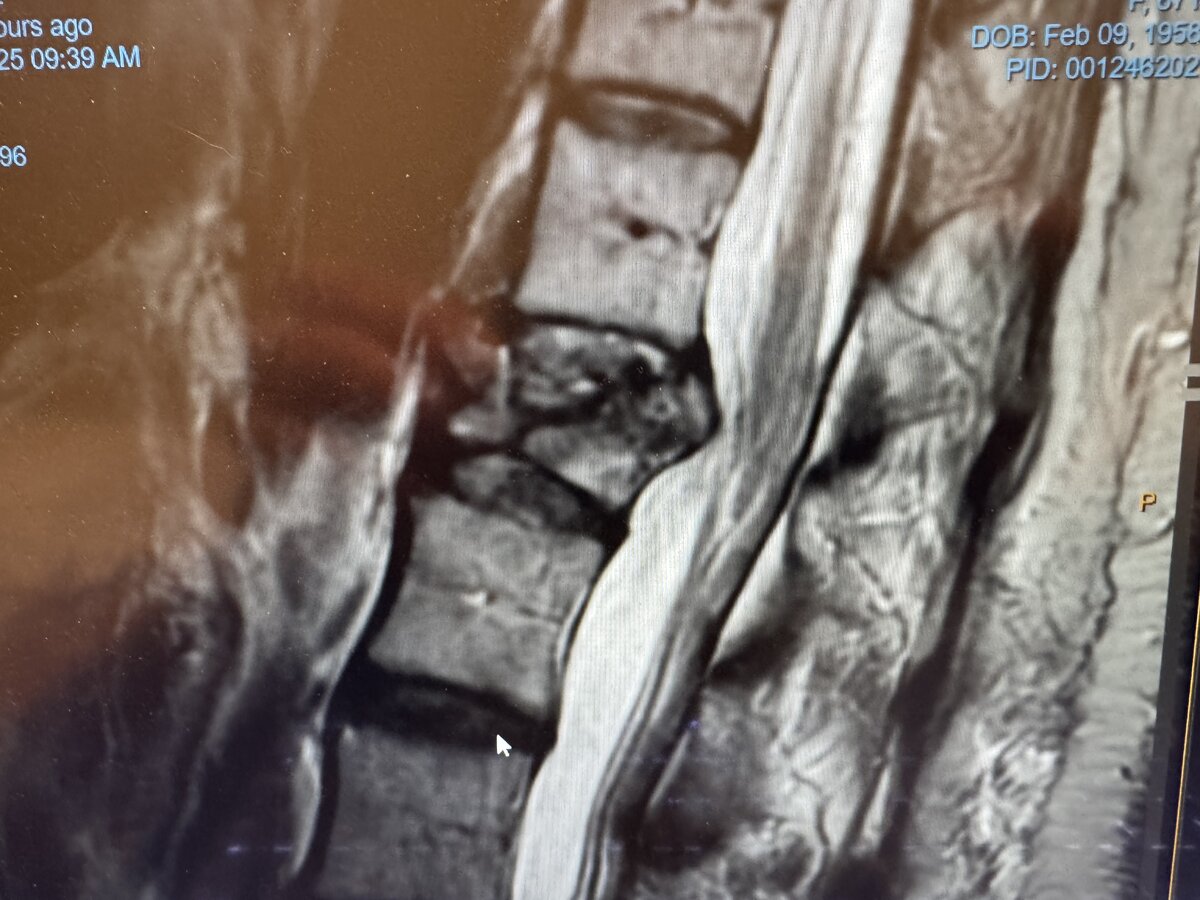

Would appreciate thoughts on if this is epidural. I had good LOR felt the pictures looked epidural. I am at a old hospital C arm is down so used the mobile XR which doesnt oblique as much as I would like. The rads dont seem confident its epidural. Patient had great relief and felt like epidural to me but would be happy to learn from others. Dont plan to do these again until I have access to Carm.

Very difficult to tell from the pictures. I don’t think it is intrathecal because on a CLO or lateral if the contrast is intrathecal it doesn’t typically sit there like a blob like your picture. The classic intrathecal appearance in a lateral is the train tracks appearance as the contrast gets dispersed through the CSF much easier than it does through the epidural space and the contrast follows gravity to the ventral intrathecal space.

Train tracks are at the level of the cord. Lumbar myelogram spreads throughout the cauda equina, which is kind of what the AP pic looks like. Still, with non-ionic contrast, preservative-free NS and dex, then most likely no headache, no problem anyway.

There is definitely some epidural spread. I can't rule out intrathecal spread.